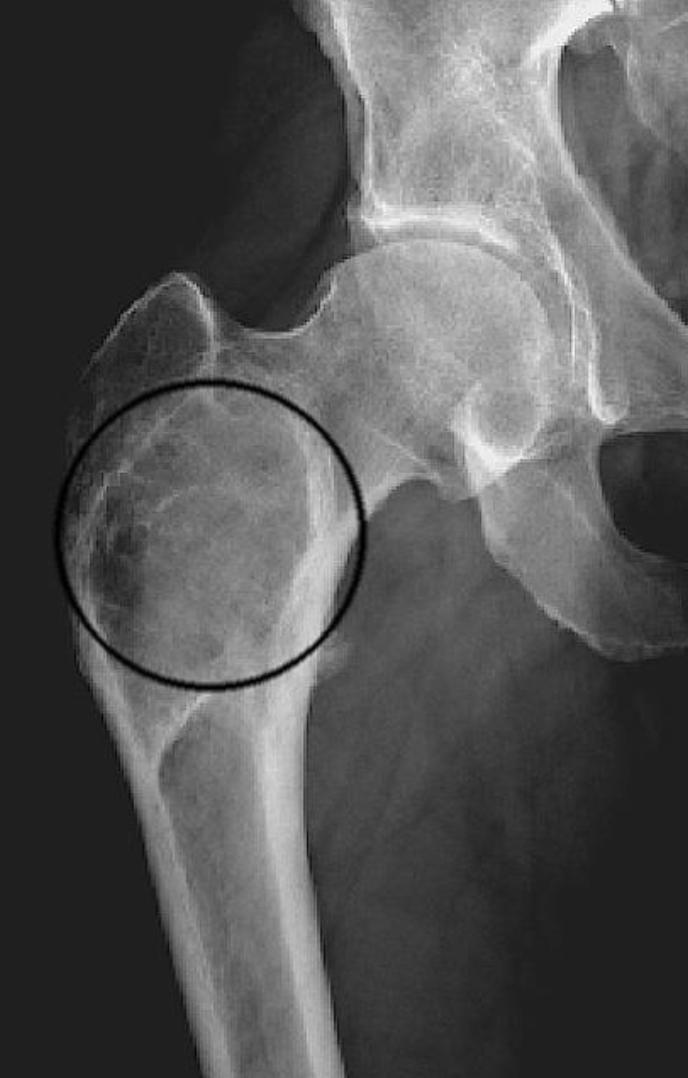

Q

X-ray shows a soap bubble osteolysis and Shepherd’s crook deformity - what disease is it likely to be?

A

Fibrous dysplasia

Shepherd’s crook deformity: coxa varus angulation of the proximal femur, classically seen in femoral involvement